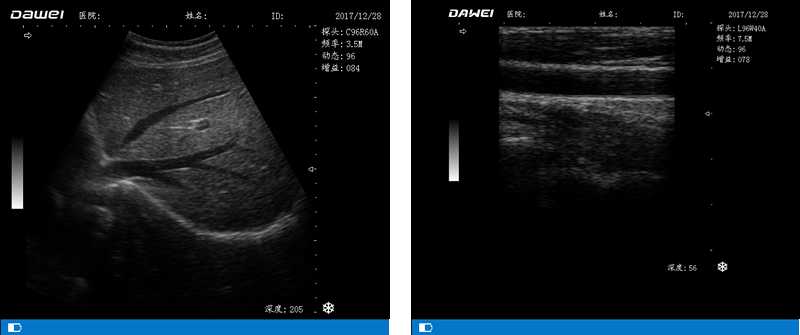

DW-500(技術版)全數字超聲診斷儀-筆記本式黑白B超機

DW-500

筆記本全數字超聲診斷儀

高陣元 高清晰度 多功能

多倍率顯示 病變診斷更準確